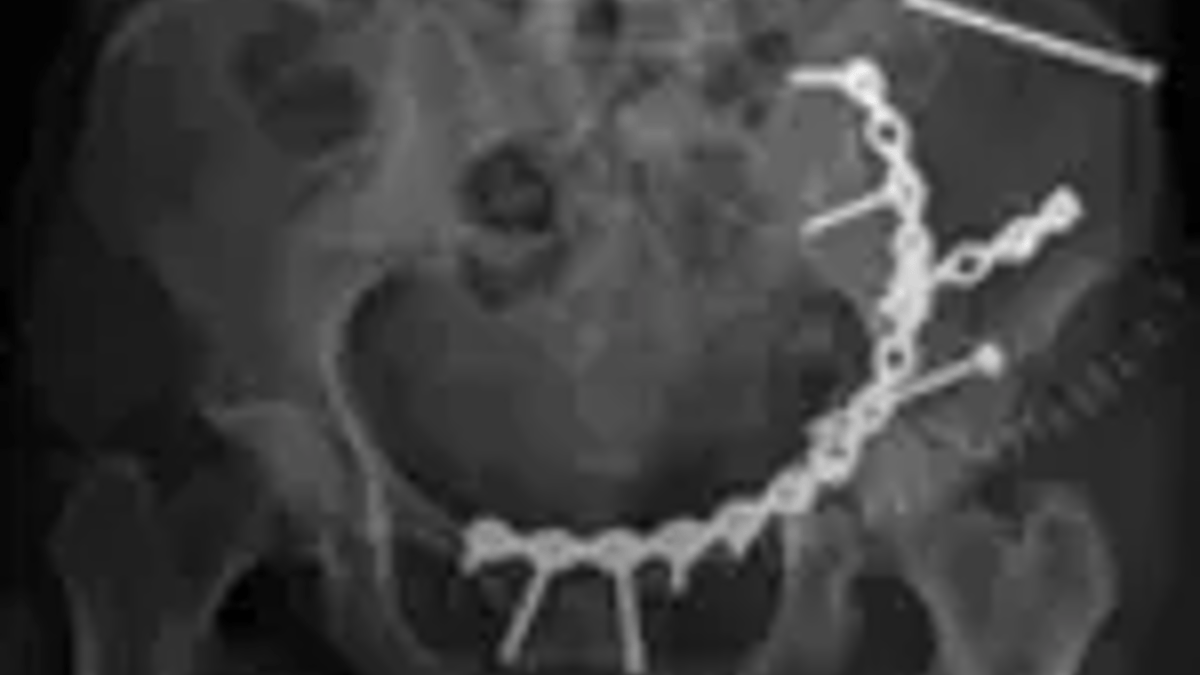

Personer som opererats för svåra bäckenskador efter allvarliga olyckor är relativt nöjda med sin livskvalitet och har i stor utsträckning återgått till sin ordinarie livsföring, visar studier vid ortopedkliniken, Akademiska sjukhuset i Uppsala där man följt denna patientgrupp under flera år.

– Främsta syftet med studierna är att genom systematiserad uppföljning av patienter förbättra vården och omhändertagandet av denna patientgrupp. Skador på bäckenet är ganska ovanliga och allvarliga skador som påverkar personen både fysiskt och psykiskt, säger doktor Tomas Borg, ortoped på Akademiska sjukhuset och ansvarig för studien.

På Akademiska sjukhuset opereras 50-70 personer varje år för svåra bäckenskador, vilket är mer än hälften av alla i landet. De skadade kommer från hela landet, många transporteras hit i ambulanshelikopter. Förutom trafikolyckor är fall från hög höjd, exempelvis från stegar eller på byggarbetsplatser de vanligaste skadeorsakerna